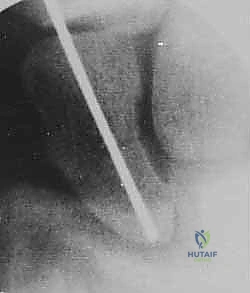

تقنية "التثبيت عن طريق الجلد" (Percutaneous Fixation) هي إجراء جراحي طفيف التوغل (Minimally Invasive). بدلاً من فتح الرسغ، يقوم الجراح بإجراء ثقب صغير جداً في الجلد (لا يتجاوز 3-5 مليمترات). من خلال هذا الثقب، وباستخدام جهاز الأشعة السينية المباشر في غرفة العمليات (C-arm Fluoroscopy)، يتم إدخال سلك توجيهي دقيق، ثم يتم إدخال مسمار خاص يسمى "مسمار ضغط بدون رأس" (Headless Compression Screw) مثل مسمار هيربرت (Herbert Screw).

هذا المسمار العبقري يتم دفنه بالكامل داخل العظم (تحت سطح الغضروف حتى لا يحتك بالمفاصل الأخرى)، ويتميز بوجود أسنان لولبية (Threads) في طرفيه بمسافات مختلفة. هذا التصميم يجعله يسحب طرفي الكسر ويضغطهما معاً بقوة هائلة (Compression)، مما يحفز التئام العظم بسرعة فائقة ويمنع أي حركة بين طرفي الكسر.

الخطوة 2: تحديد مسار المسمار بدقة (Guidewire Placement)

هذه هي الخطوة الأكثر أهمية والتي تتطلب مهارة استثنائية. يقوم د. هطيف بعمل شق صغير جداً (بضعة مليمترات). باستخدام جهاز الأشعة، يقوم بإدخال سلك معدني